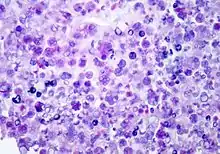

P. wickerhamii has a round to elliptical cell shape measuring 3–11 µm in diameter. The organism has thick wall (theca) with internal septations that form the small wedge-shaped endospores, which are arranged radially and moulded (morula-like form).[1] Reproduction is asexual by release of the spores from the sporangia, which can occur every 5–6 hours in ideal conditions.[2]

Diagnosis can be made through culture of diseased tissue in Sabouraud dextrose agar or by visualization of sporangia containing sporangiospores on tissue biopsy (using hematoxylin/eosin, GMS, or PAS histochemical stains). The organism incites a chronic granulomatous inflammation with infiltrate of histiocytes, lymphocytes, giant cells and occasional eosinophils.